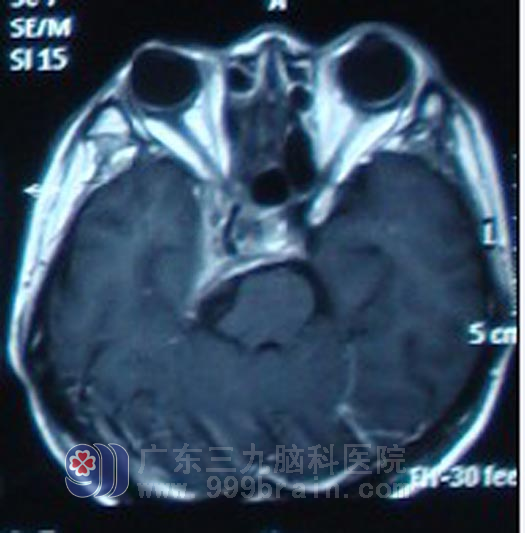

今年3月,吴先生再次出现恶心,并伴有右眼视力下降,再次复查鼻咽CT提示肿瘤较2010年5月有所增大。4月11日,吴先生在外院就诊过程中突发烦躁,胡言乱语,四肢不自主活动等症状,急诊送入广东三九脑科医院肿瘤综合治疗中心求进一步治疗,来院后急行CT示:右侧海绵窦占位性病变,压迫脑干,脑室扩大、脑积水。4月12日急诊在全麻下行脑室外引流术,4月13日开始行急诊放疗,病情逐渐好转。4月18日拔除引流管,吴先生已无烦躁胡言乱语症状,未出现头痛恶心呕吐等不适。随后行复发肿瘤区域成放疗及辅助化疗。现在吴先生康复良好,肿瘤基本消失,定期会院复查。http://www.999brain.com/

放疗后